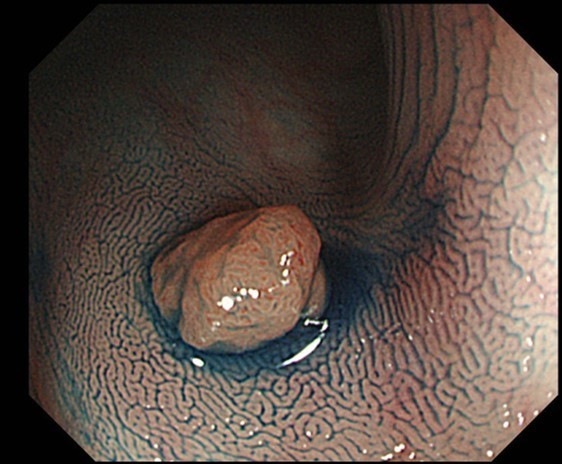

このような症状があるかたは、大腸ポリープや大腸がんが原因であったり、潰瘍性大腸炎/クローン病といった腸の炎症による病気が原因であることがあります。 もちろん痔(内痔核)などの良性疾患が原因のこともありますが、最近は年齢が若い方で大腸がんが見つかり治療が必要な方もいます。

早期発見であれば内視鏡治療によりおなかを切らずに治療することができる可能性が高くなります。上記のような症状が続く方には検査をお勧めします。